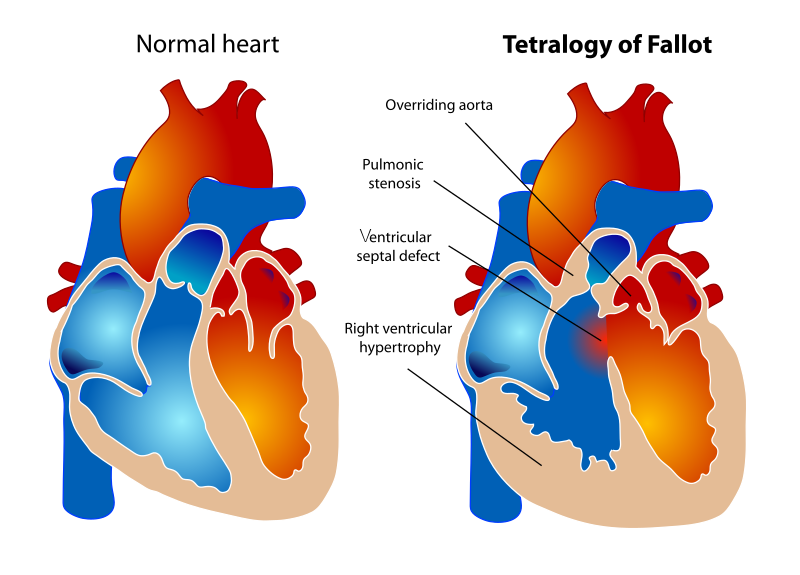

Tetralogy of Fallot (ToF)

Tetralogy of Fallot (ToF) is a congenital cardiovascular anomaly that includes:

- Right ventricular outflow tract stenosis

- Right ventricular hypertrophy

- Ventricular septal defect (VSD)

- An overriding aorta

Early cyanosis is caused by right-to-left shunting, and the degree of stenosis dictates how much shunting and cyanosis is present.

In response to a cyanotic spell, patients with tetralogy of Fallot (ToF) are taught to squat because:

- Artery resistance is increased.

- Reduces shunting and increases blood flow to the lungs

Tetralogy of Fallot (ToF) radiology of the heart shows a “boot-shaped” heart.